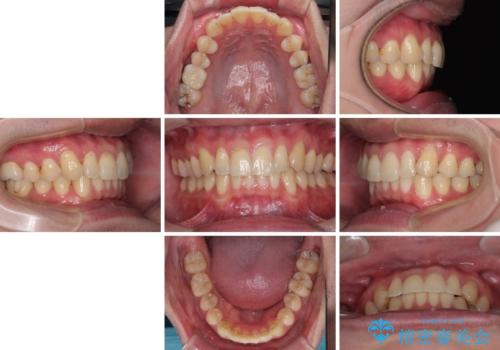

上下のデコボコを治したい インビザラインによる矯正治療

お仕事が忙しく、1日の装着時間は不十分となる日もありましたが、治療は順調に進めていくことができました。

途中、以前大きなむし歯で処置をした歯が痛み出し、根管治療が必要となったため、根管治療とオールセラミッククラウンによる補綴治療を行い、その後にインビザラインによる仕上げの歯列移動を行い、無事に治療を終えることができました。